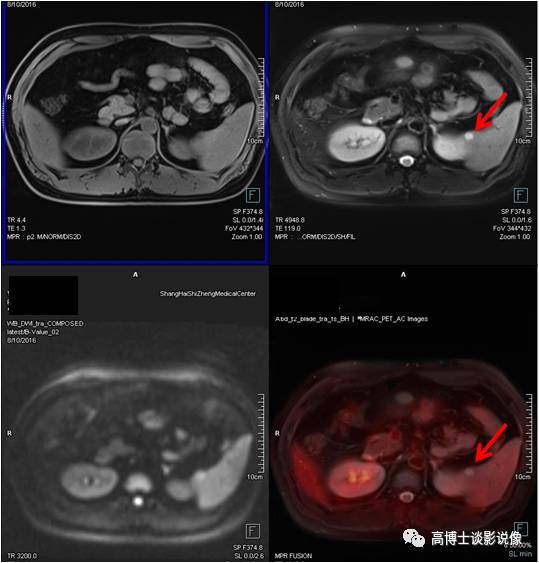

血管平滑肌脂肪瘤

中年女性,甲状腺肿瘤术后复查。右肾中部见直径约2.5cm异常信号灶,内含脂肪信号,FDG无代谢,诊断为血管平滑肌脂肪瘤。

点评

血管平滑肌脂肪瘤(以往称错构瘤)是肾良性肿瘤中最常见者,约占肾肿瘤的3%。肿瘤较小者,可以B超定期随访复查;巨大的肿瘤会压迫邻近脏器,且容易发生出血,引起腹痛等急症,应避免剧烈运动及外伤。